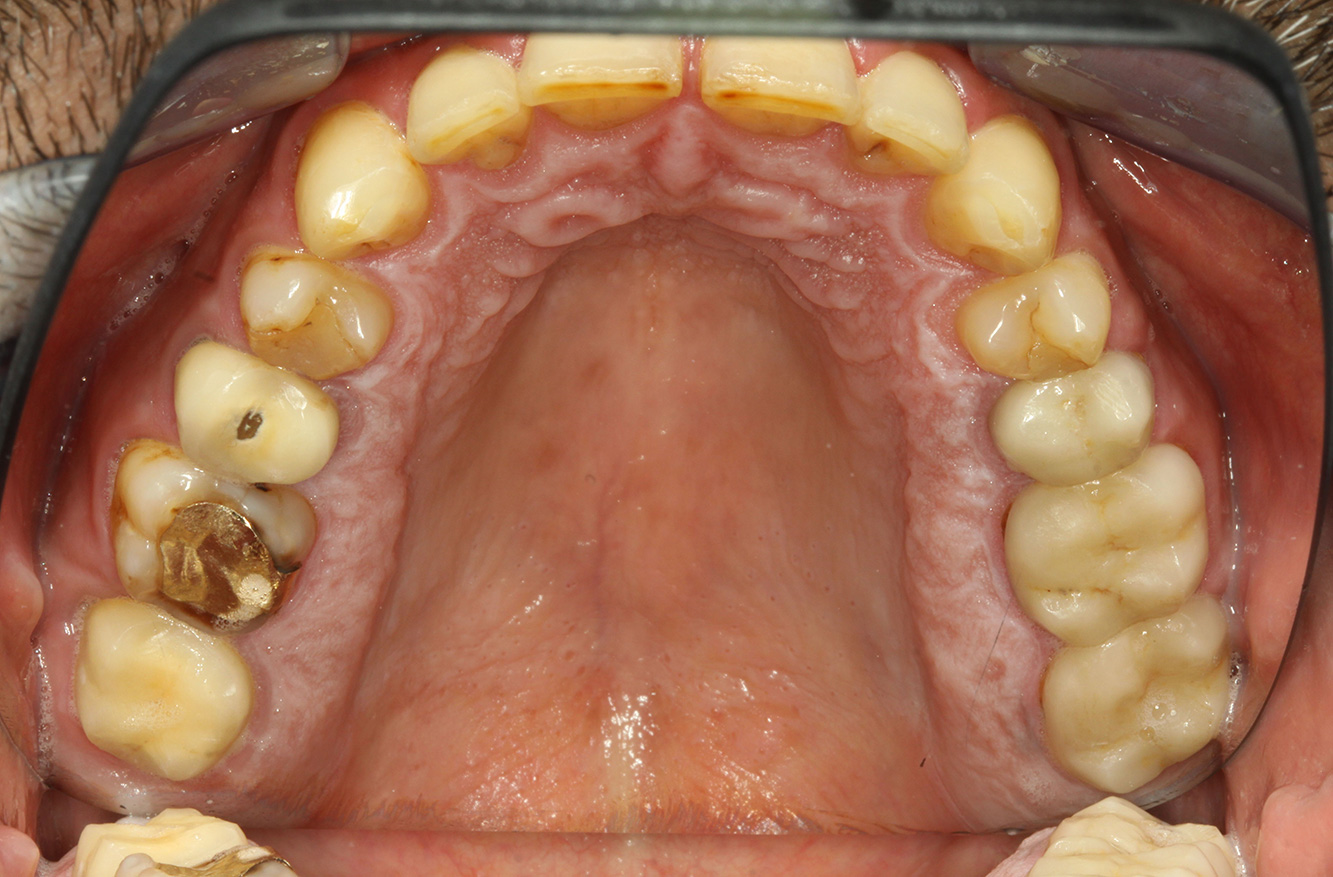

Paciente con endocarditis con lesiones de caries activas*

El paciente tiene 39 años con valvuloplastia frente a una insuficiencia valvular y endocarditis. Toma regularmente ASS 100 (ácido acetil salicílico) como anticoagulante. En el ámbito del estilo de vida, la alimentación se identifica como promotora de caries, ya que suele consumir alimentos azucarados y seis o siete comidas al día. La salud oral del paciente muestra un riesgo medio de caries con lesiones activas. El riesgo de periodontitis es bajo, presenta gingivitis. Se hacen las siguientes recomendaciones para el tratamiento profiláctico.